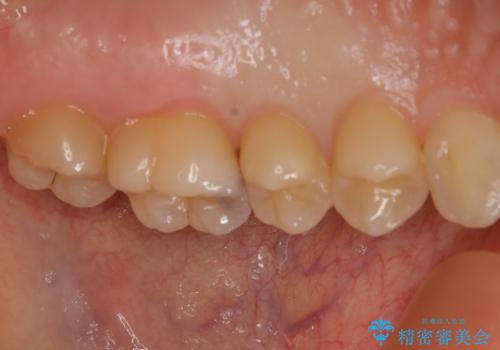

大臼歯 大きな虫歯をセラミックインレーに

- 歯が黒くなってきているのが気になるとのことで、レントゲンを撮影し診断を行いました。

幸い神経までは到達していない虫歯だったため、部分的な詰め物「インレー」で治療を行うこととなりました。